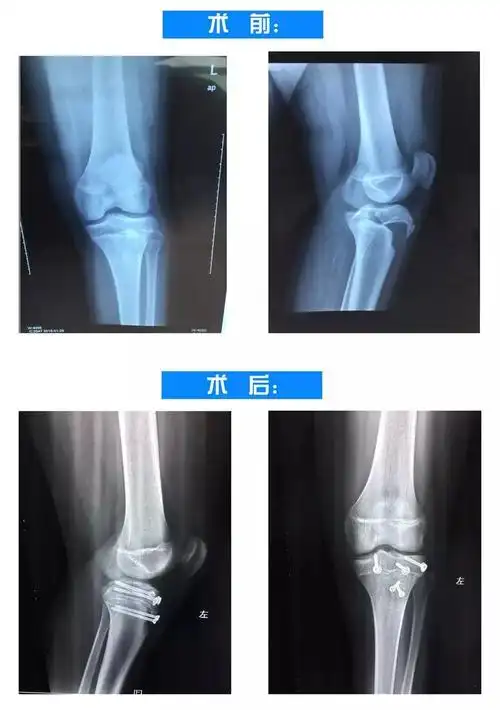

小儿胫骨远端干骺端骨折伴骨骺滑脱

胫骨干骺端骨折

超难挑战!15岁胫骨干骺端骨折

12岁儿童胫骨远端三平面骨骺骨折

左胫骨骨骺骨折

【医疗技术】罕见!一名青少年胫骨近端骨骺损伤,骨一科团队这样处理